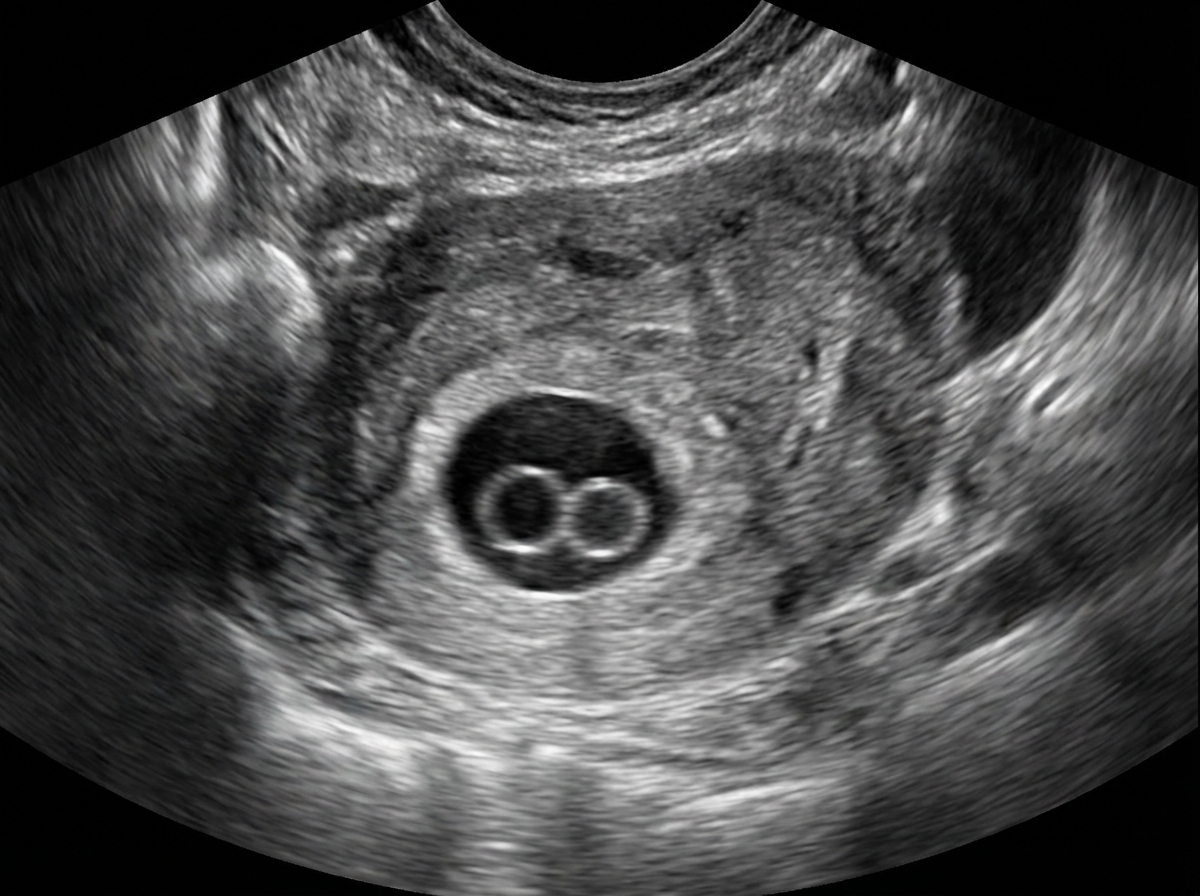

Double bleb sign seen in early pregnancy is due to?

Explanation: ***Yolk sac and amniotic sac*** - The **double bleb sign** on ultrasound refers to the separate visualization of the **yolk sac** and the **amniotic sac** within the gestational sac. - This sign is a crucial indicator of a **viable intrauterine pregnancy** in the early stages, typically between 5.5 and 6.5 weeks of gestation. *Amnion and chorion* - The **amnion** and **chorion** are membranes that form later in pregnancy and eventually fuse. - While they are distinct structures, their visualization does not constitute the "double bleb sign," which specifically refers to the distinct spaces of the yolk sac and amniotic sac. *Chorion and decidua* - The **chorion** is the outer fetal membrane, and the **decidua** is the modified endometrium during pregnancy. - While both are important structures in early pregnancy, they are not the structures visualized in the double bleb sign. *Twin pregnancy* - A **twin pregnancy** would involve two separate gestational sacs or, in the case of monochorionic-diamniotic twins, two amniotic sacs within one chorion, each containing a fetus. - The double bleb sign is a feature of a **single intrauterine pregnancy** and is not indicative of twins.